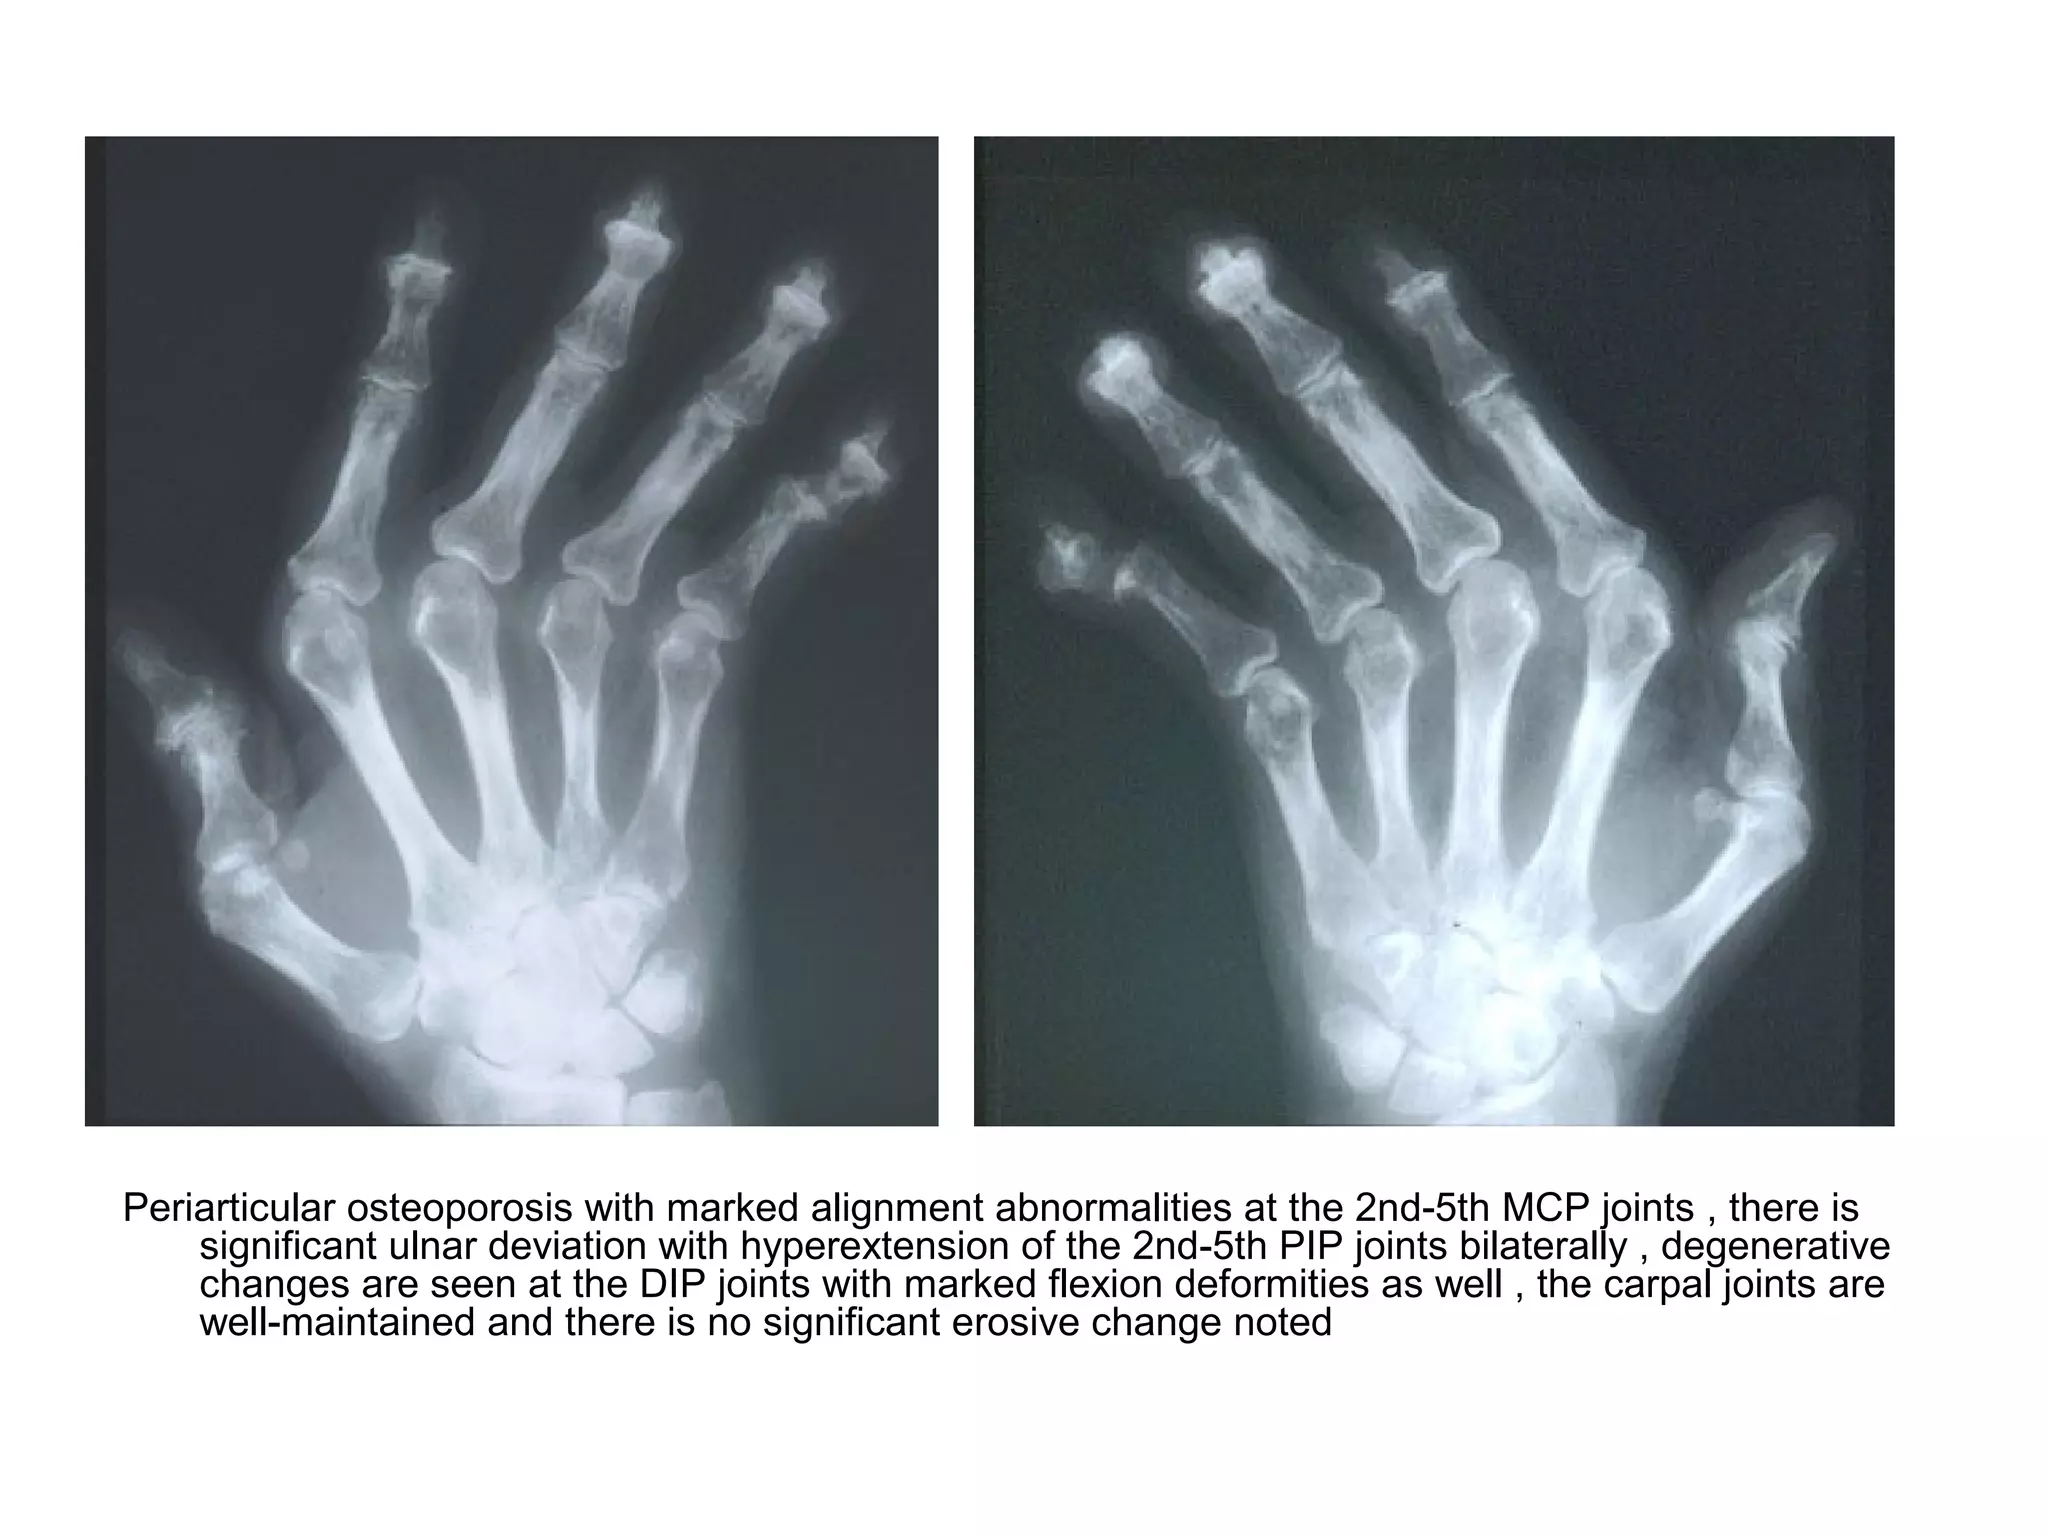

Periarticular osteoporosis with marked alignment abnormalities at the 2nd-5th MCP joints , there is

significant ulnar deviation with hyperextension of the 2nd-5th PIP joints bilaterally , degenerative

changes are seen at the DIP joints with marked flexion deformities as well , the carpal joints are

well-maintained and there is no significant erosive change noted